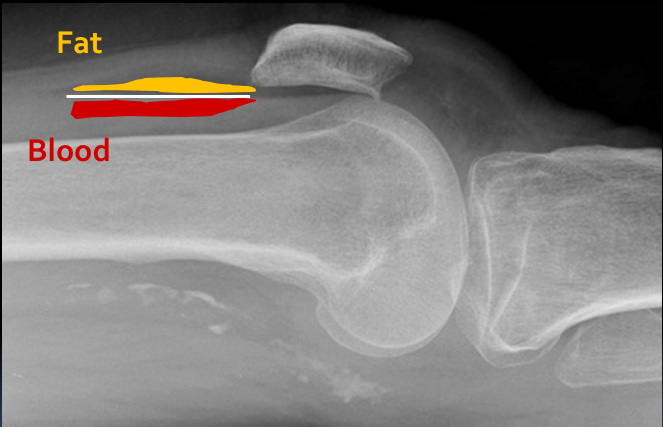

A 30 year old man presented to the ED with left knee pain after a cycling accident.

On examination there was no deformity, but it was painful for him to weight-bear. Movements of his knee were painful, and this limited his movements.

What is a lipohemarthrosis?

Results from an intra-articular fracture with escape of fat and blood from the bone marrow into the joint, and is most frequently seen in the knee.